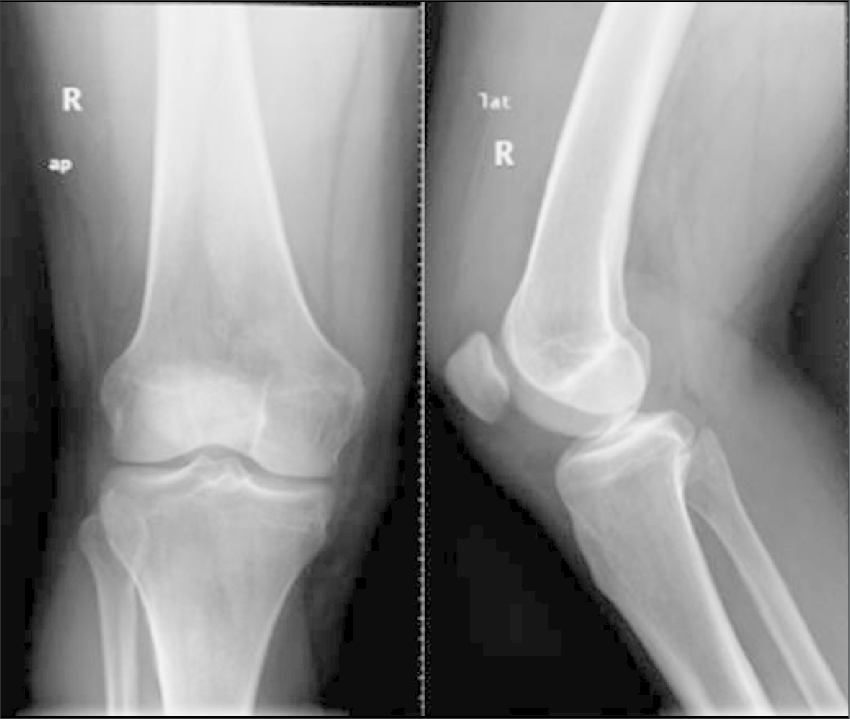

Digital X ray

Digital radiography is a form of X-ray imaging, where digital X-ray sensors are used instead of traditional photographic film. Advantages include time efficiency through bypassing chemical processing and the ability to digitally transfer and enhance images. Also, less radiation can be used to produce an image of similar contrast to conventional radiography. Instead of X-ray film, digital radiography uses a digital image capture device. This gives advantages of immediate image preview and availability; elimination of costly film processing steps; a wider dynamic range, which makes it more forgiving for over- and under-exposure; as well as the ability to apply special image processing techniques that enhance overall display quality of the image. Digital radiography significant features include; Higher quality of care since exposure to radiation is reduced by 75%, X-ray image enhancement, Enhanced X-ray image quality, No chemical developers since it eliminates film processing, Time and productivity savings.